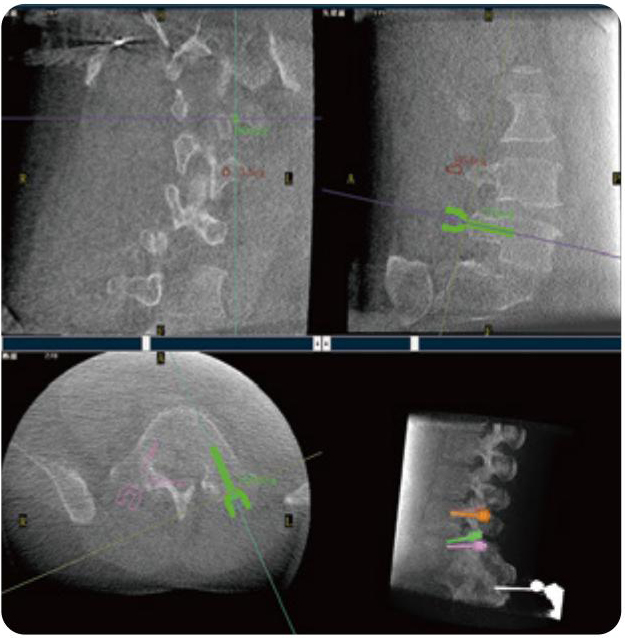

Clinical picture

临床图片